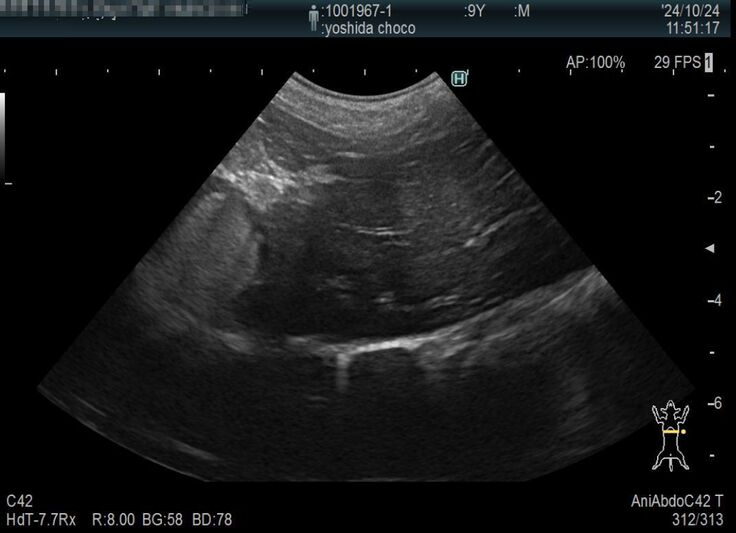

以前より下部尿路疾患で尿路結石を持っているチョコですが、膀胱にある結石が大きくなり膀胱を痛めて膀胱炎を頻繁に発症するようになりました。

膀胱炎から炎症が全身に、更には脾臓の腫瘍が確認されました。

膀胱炎の資料をご覧ください。

検査結果もかなりの異常さが分かると思います。

現在9歳のチョコですが、脾臓はいずれ摘出した方が良いと獣医師より指摘されております。まだ若いので悪性の可能性は低いと言われています。また、結石も同時に摘出をした方が良いと。

検査の結果、脾臓肥大が限界近くの爆発寸前になっていることが判明しました。

脾臓は4センチまでなってるから、いつ破裂してもおかしくない状況。